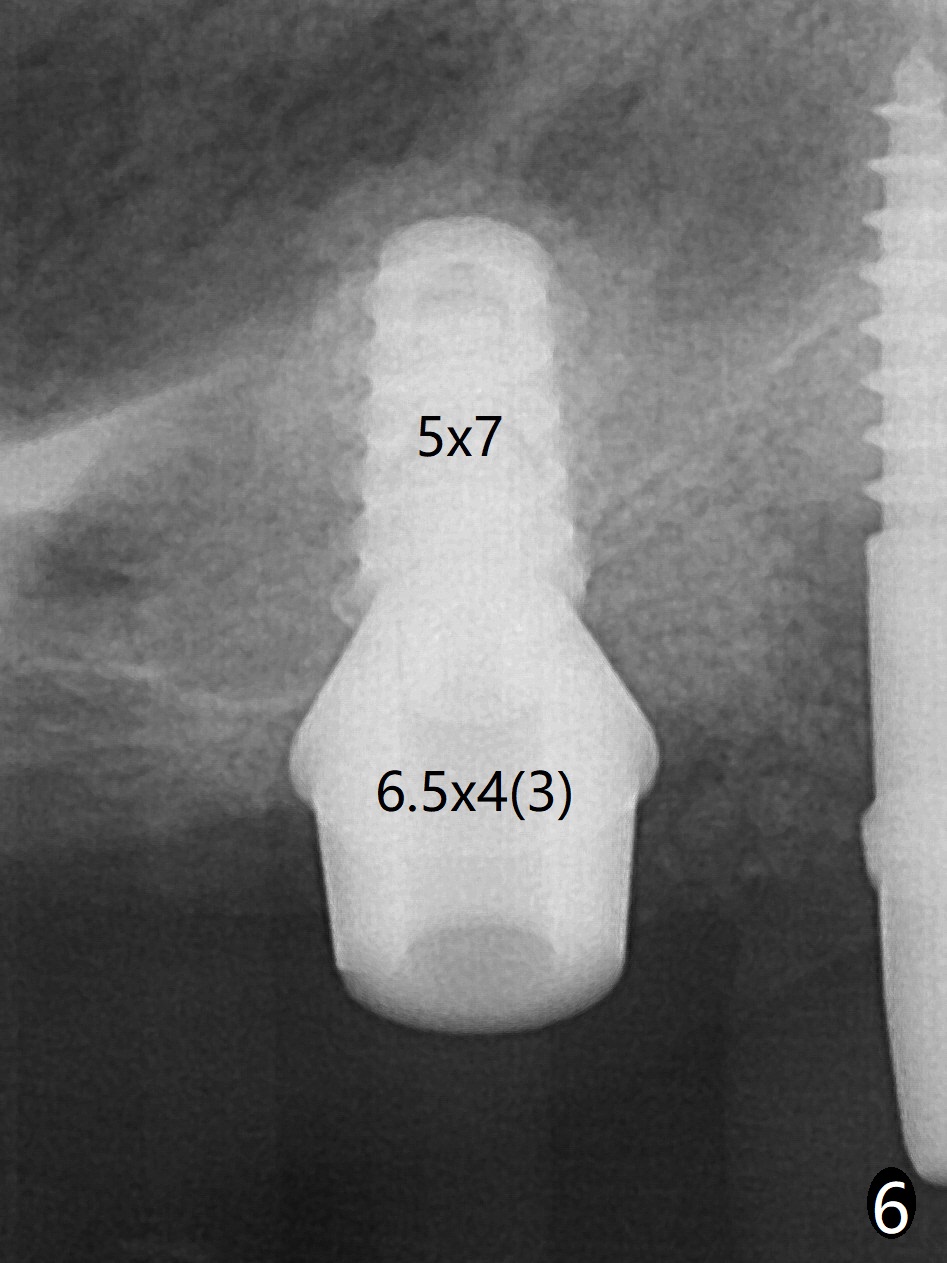

术前清晨复习3号牙窦底,中央是植骨(图一,二:*(皮质骨:密度高,质地可能软)),由于窦底斜坡,术前估计穿孔可能最先发生在远中,术中的确如此(图三:<(使用4毫米钻头后)),放置粘性骨粉(图四),利用导板(图五:G)和4x9毫米报废植体提升(*)。使用4.5毫米钻头,放置半张PRF膜,骨粉,5x7毫米植体以及修复基台,最后在后两者周围放置骨粉(图六,七:*(腭侧一个螺纹暴露)),覆盖1/2PRF膜,缝合,树脂敷料。